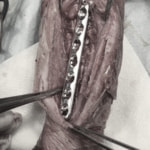

脊髄の減圧、脊柱管の再構築・安定化を目的に、片側椎弓切除術およびMatrixMANDIBLE Plateによる椎体固定を実施しました。

隣接椎体を架橋するようにプレートを設置しました。